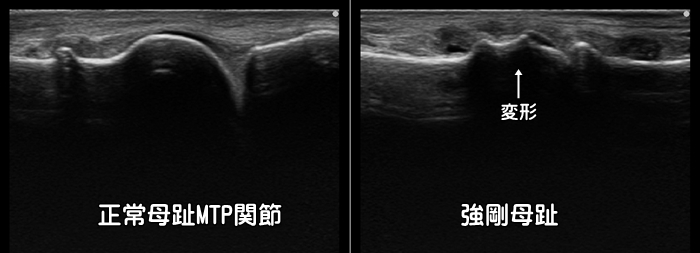

強剛母趾

足の母趾を上に反らした際に、母趾の甲側に痛みがあれば強剛母趾(きょうごうぼし)を疑います。

簡単に言うと足の趾の関節の変形性関節症です。跪座(きざ)と呼ばれる体勢で痛みが出現します。